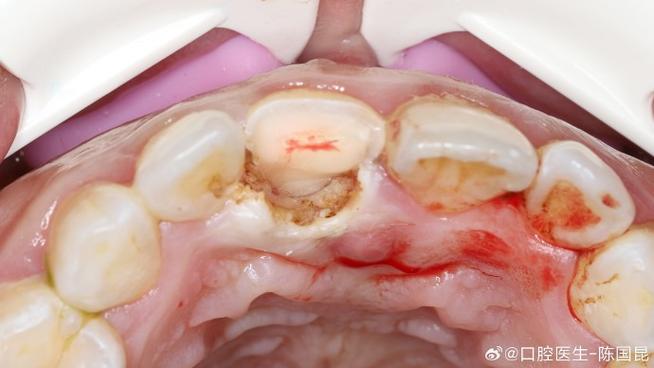

种植牙植骨手术中的创伤面主要指手术操作导致的骨组织、软组织(牙龈、黏膜)的缺损或损伤,根据发生部位和性质可分为以下几类:

这是植骨手术的核心创伤面,主要由患者自身骨量不足引起,长期缺牙后牙槽骨发生吸收、萎缩,或因外伤、肿瘤切除导致骨缺损,为容纳种植体,需通过植骨材料(如自体骨、异体骨、骨替代材料)重建骨组织,形成骨缺损区的“填充性创伤面”,种植窝预备过程中,若钻头转速、冷却不当,可能导致骨组织热损伤,形成“热灼伤创伤面”,影响骨细胞活性。

植骨材料(如骨粉、骨膜)植入后,与自身骨组织、软组织接触的界面存在“生物机械性创伤面”,材料颗粒间可能残留死腔,若与血液、组织液结合不充分,易形成纤维包裹,影响骨整合。

术后患者因咬合创伤、口腔卫生维护不当(如过早用患侧咀嚼、刷牙力度过大),导致植骨区受力异常,或机械性摩擦创口,引发继发性创伤面,表现为黏膜破溃、植骨材料暴露。